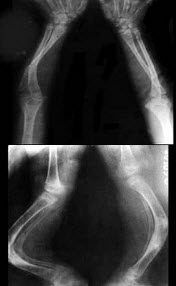

9、单项选择题

男,根据其正常骨盆影像图像,判断其最可能的年龄()

A.6岁左右

B.30岁左右

C.12岁左右

B.右肺炎症

C.纵隔肿瘤

D.右肺肿瘤

E.右肺结核

男,9岁,左肘外伤,结合图像,最可能的诊断为()

A.左肱骨内上髁骨骺1度分离

B.左肱骨内上髁骨骺2度分离

C.左肱骨内上髁骨骺3度分离

D.左肱骨内上髁骨骺4度分离

E.左肱骨内上髁骨骺5度分离

男,62岁,左膝疼痛、活动不便,结合图像,最可能的诊断是()

A.髌骨软化症

B.粉碎性骨折

C.膝关节结核

D.退行性骨关节病

E.风湿性关节炎